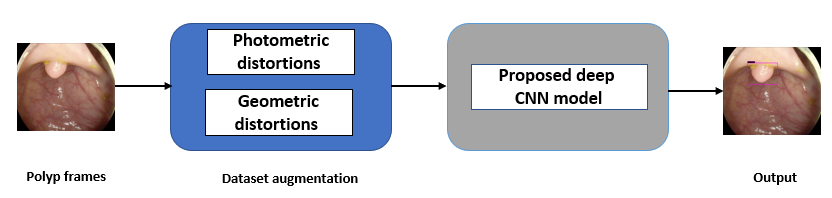

This work presents a new-CNN based detection model of polyp in colonoscopy images. The proposed CNN model employs fewer hidden layers, making the model lighter and less time-consuming during training. The proposed CNN model employs MISH as an activation function in some of the hidden layers for better deep propagation of information within the CNN [21]. Data augmentation such as photometric and geometric distortions is performed due to the scarcity of annotated polyp images generated from the colonoscopy process. The rest of the paper is categorized as follows: Section 2 presents recent related work done on polyp detection in colonoscopy images using DL. In Section 3, the proposed CNN model for polyp detection in colonoscopy images is explained in detail. in Section 4, the experimental results are described in detail, along with the dataset acquisition and augmentation process. Finally, in Section 5 the paper is reviewed and concluded and future work is presented.

Fig. 1 shows the general flow of the proposed approach for polyp detection in colonoscopy images. As shown in Fig. 2, the proposed deep CNN consists of 16 convolutional layers, two fully connected layers, and a softmax layer. To lessen computational complexity and improve hierarchical image features, maxpooling is used for the first 15 convolutional layers. For better image feature extraction, different sizes of convolution kernels are employed, with a stride of 2. In the proposed model, we have implemented Mish [21], which is a self-regularized smooth non-monotonic activation function, in the first 15 convolutional layers. This implementation was done after extensive trials to find the best matching position of the activation function. As observed in Fig. 3, Mish is an unbounded above result in avoiding saturation due to capping. This may normally lead to slow training, i.e., near-zero gradients. A better gradient flow and smooth propagation of information across deeper layers are achieved by the infinite order of continuity and a small allowance of negative values, in comparison to a strictly bounded rectified linear unit (ReLU) as an activation function. MISH can be expressed mathematically as:

The study used a publicly available dataset of polyp-frames obtained from the ETIS-Larib database [34], containing 196 polyp images. These images were obtained from 34 different colonoscopy videos of 44 different polyps with various appearances and sizes, having a resolution of pixels. The ground truth of polyp areas for polyp datasets is determined by expert video endoscopists. A CNN model trained with such a small amount of data is likely to be meaningless and unstable, so data augmentation was performed on the polyp dataset. Data augmentation had to be performed on the colonoscopy images by considering vivid variations. Otherwise over-fitting would have occurred. In a colonoscopy imagery, polyps exhibits large variations in location, color, and scale. Moreover, variations in brightness and definition also occur due varrying the view-point of the camera. Therefore, in addition to photometric distortions and geometric distortions, we also have considered zooming, shearing, and altering brightness as strategies for data augmentation.

For photometric distortions, we controlled brightness and contrast as an enhancement, while blurring by adding noise with a standard deviation of 1.0. Similarly, for geometric distortions, clock-wise rotation of the polyp images with angles of , , and were performed. Zoom-in and zoom-out with zooming parameters such as 30.00% and 10.00% were performed to obtain different scales of polyp images. Lastly, shearing for both the x-axis and the y-axis was performed to shear the images from left to right and top to bottom, respectively. Fig. 4 shows photometric and geometric forms of image augmentation. In this way, we augmented the data set of the ETIS-Larib database from 196 polyp images to 2,156 images, which is more suitable for training the proposed deep CNN model.